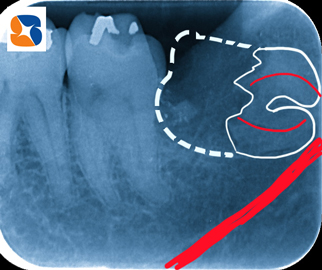

〈抜歯中の診断〉

歯の根が湾曲している(ストレートではない)

→骨に引っ掛って、出てこない。

抜歯開始から、40分。ようやく、内に折れ曲がった2本の根を抜いて、抜歯が完了しました。